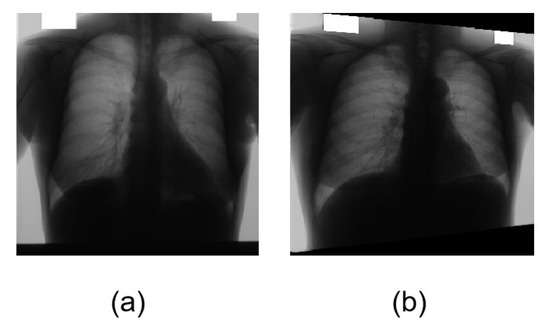

The original image for transformation and organs segmentation in Figure 4. The Japanese Society of Radiological Technology (JSRT) [32] is a public dataset of chest X-ray images with accurate annotation for lung fields and heart masks. JSRT encompasses 154 nodule and 93 non-nodule 12-bit gray-scale images with high resolution 2048 × 2048. As we know, machine learning needs massive amounts of data to optimize the model and avoid overfitting. The medical images used in the experiment are provided by Shenzhen No.3 Hospital in Shenzhen [33]: 340 normal X-ray images and 275 abnormal X-ray images. The total number of original images is 862. We use geometric transformations and rotation for data augmentation to increase the data to avoid gradient explosion. In this paper, the adaptive histogram equalization (CLAHE) operation is used for image enhancement. Data augmentation is a common method used in image processing for medical image segmentation and classification because public datasets with accurate annotation are commonly small, which can cause overfitting. Common data augmentation techniques can be divided into basic image manipulation and deep learning approaches. The heart part and the lung part of all pictures are marked by the doctor. All algorithms use 70% as the training sample and 30% as the test sample and all images are converted to 512 × 512 pixels PNG format.

Figure 4. Chest X-ray images. (a) The original chest X-ray medical image. (b) The figure is transformed with rotation.